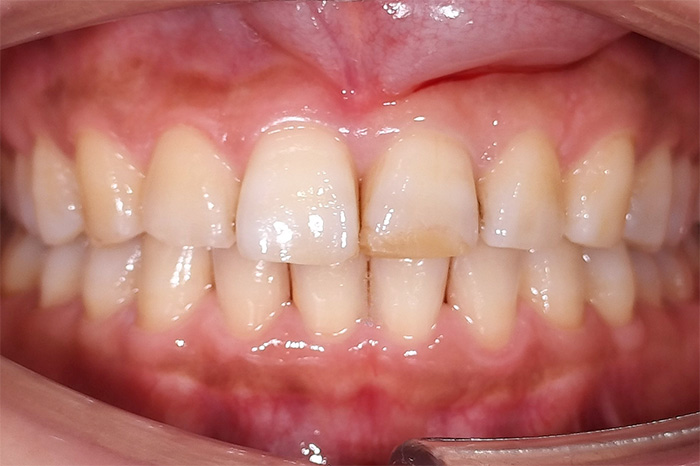

Before

After

前歯の見た目と噛み合わせのバランスを整えたケース

「前歯が強くかみ込んでいる気がする」「歯並びだけでなく、噛み合わせも気になる」

今回の患者様は、ディープバイト(過蓋咬合)による前歯の見た目と噛み合わせを気にされて来院されました。ディープバイトとは、上の前歯が下の前歯に深く重なっている噛み合わせのことで、見た目の問題だけでなく、前歯や顎への負担につながることがあります。

本症例では、マウスピース型矯正装置(インビザライン)を用いて治療を行いました。合計84枚のアライナーを使用し、歯並びだけでなく咬合の深さにも配慮しながら治療を進めました。

治療後は、前歯の見た目のバランスが整い、噛み合わせも改善しました。